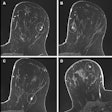

The use of preoperative breast MRI to improve surgical staging has increased, especially among women with dense breasts, extensive ductal carcinoma in situ (DCIS), and lobular histology, the team explained. But Black women are less likely to undergo this exam -- putting them at risk of additional surgery. Ginzberg's group investigated whether the use of preoperative MRI after breast cancer diagnosis varies by race and insurance type and whether undergoing the exam is associated with downstream surgical management.

"[Our] study adds an essential dimension to the existing literature by demonstrating that, even after adjustment for breast density and inclusion of a diverse multipayer cohort, Black women are still less likely to undergo preoperative MRI compared with white women," they wrote.